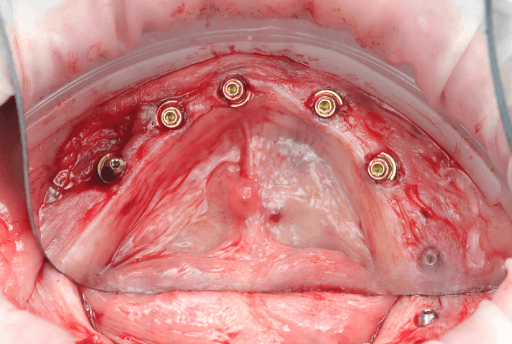

During the second appointment, the surgical implant placement was performed. Using the 3D printed surgical guides, seven implants were placed in the upper arch and six implants in the lower arch. The surgery was performed under local anesthesia using a flapless approach in both arches. Total surgical time was approximately 45 minutes. No intraoperative complications were observed.

Upper arch pre-surgical intraoral situation

3D printed surgical guide with fixation pins

Seven implants placed

Upper arch surgical procedure. From left to right: Pre-surgical intraoral situation, 3D printed surgical guide with fixation pins, and seven implants placed.